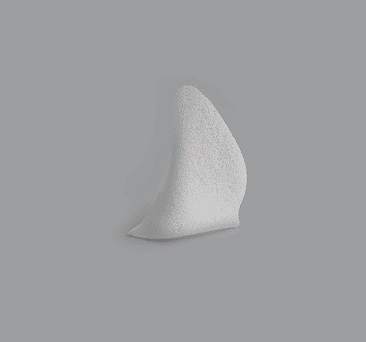

Conical Orbial Implant